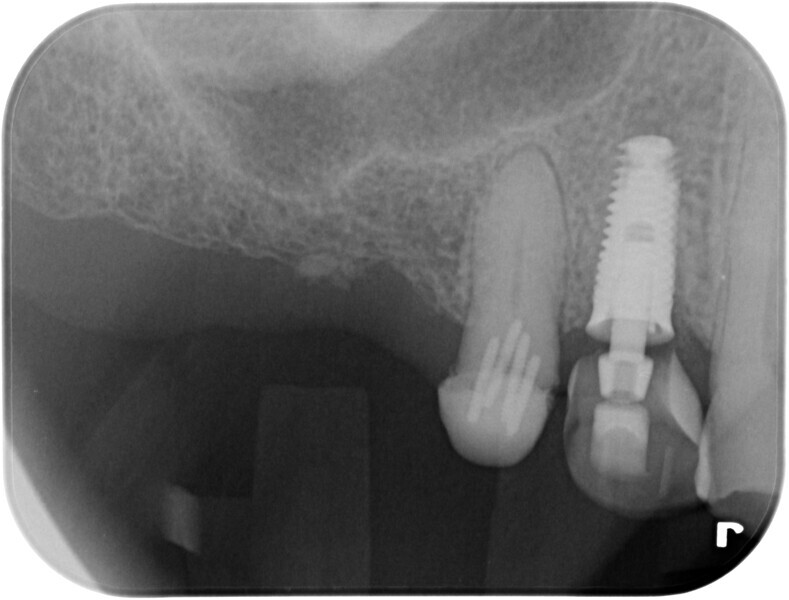

Tooth #14 was deemed unrestorable, and so it was decided to extract the tooth (Figs. 3 & 4), wait for bony healing and replace it with an implant with a provisional restoration. During the healing process, endodontic therapy would be performed on tooth #15. After bony integration, implant #14 would be restored with a screw-retained direct-to-implant zirconia crown, and tooth #15 would also be restored with a complete zirconia crown. A deliberately lighter shade would be chosen, factoring in the patient’s long-term desire to improve the colour of his teeth.

Fig. 3: Initial periapical radiograph.